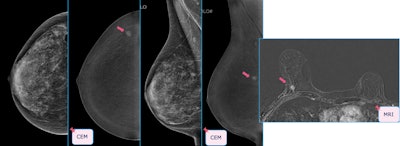

Case of a multicentric Luminal A invasive ductal carcinoma. While conventional mammography would have detected one lesion, contrast-enhanced mammography detected multicentricity, and this was confirmed by MRI. All figures courtesy of Drs. Manuel R López de la Torre Carretero, Miguel Barrio Piqueras, and Luis Javier Pina Insausti and presented at ECR 2025.